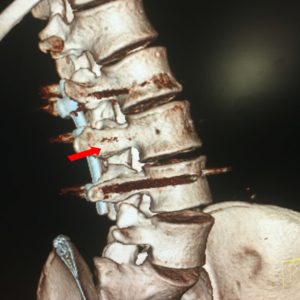

Εικόνα 9 α,β,γ,δ,ε,ζ,η,θ,ι,κ,λ,μ,ν

Αξονική τομογραφία της Οσφυϊκής Μοίρας της Σπονδυλικής Στήλης (ΟΜΣΣ), (16.06.2018) δυόμιση περίπου χρόνια μετά τη χειρουργική επέμβαση.

Οι τομές της αξονικής τομογραφίας είναι ιδιαίτερα επικεντρωμένες στο επίπεδο του (Δ) μίσχου (pedicle) του 3ου οσφυϊκού σπονδύλου, στην περιοχή όπου βρισκόταν το οστεοειδές οστέωμα.

Το δημιουργηθέν οστικό έλλειμμα γέμισε με οστικό αλλομόσχευμα.

Στις εγκάρσιες (axial) τομές της αξονικής τομογραφίας είναι εμφανής η πλήρωση του οστικού κενού και η αποκατάσταση της ακεραιότητας της περιοχής του (Δ) σπονδυλικού τόξου του 3ου οσφυϊκού σπονδύλου.

3-D (τρισδιάστατες) τομές της αξονικής τομογραφίας η, θ, ι, κ, λ, μ, ν